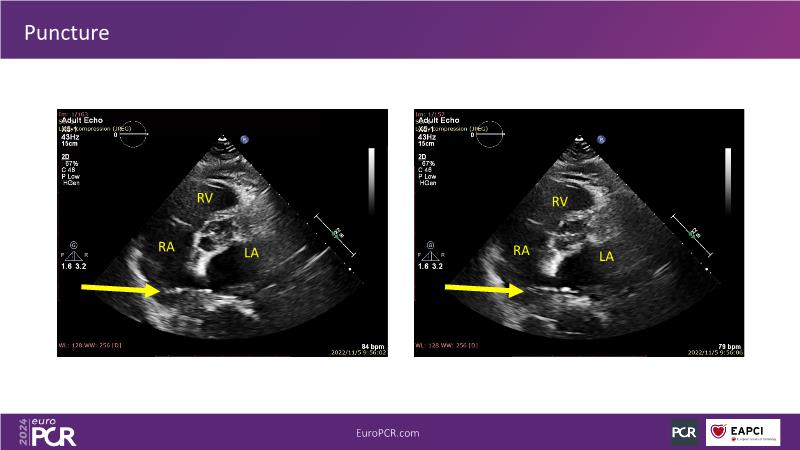

Watch this session to gain insights into the clinical evidence of mitral TEER therapy for the Asian population, learn techniques for implanting a MitraClip in patients with challenging anatomy, and understand how to use the four clip sizes for optimal outcomes. The session also covers educational aspects of clipping in dextrocardia, the benefits of reserve bending of the transseptal needle for tenting and puncture, new steering maneuvers for dextrocardia patients, and the importance of understanding anatomy and collaborating closely with the echo team for success.